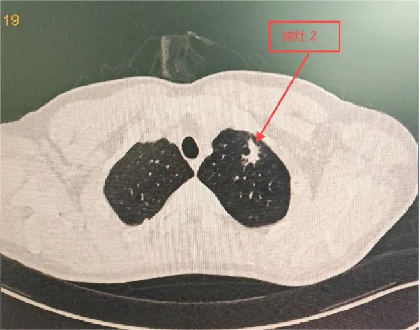

明确诊断后,主管医师予以相应的治疗方案,程大叔的咳嗽、胸痛症状迅速得到了缓解;1月后复查胸部CT,提示肺部阴影较前明显吸收;程大叔悬着的心,终于放下了。

治疗1月后